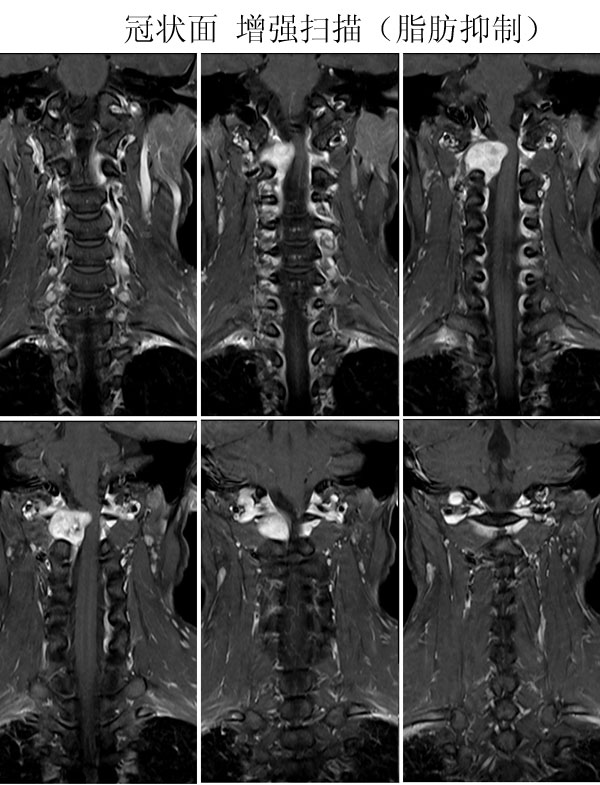

本病例来自广东同江医院

病史:女,27岁,洗头按摩时扭颈导致昏迷,检查发现颈椎占位

手术病理:

神经鞘瘤